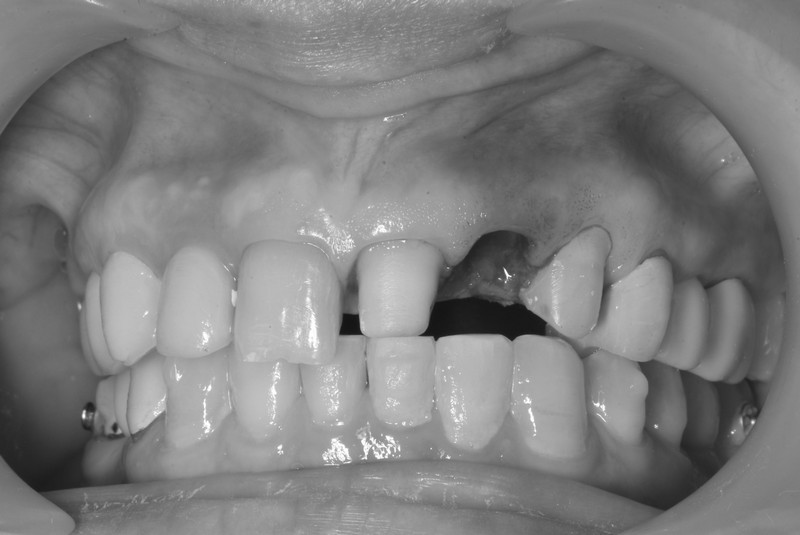

立即式植牙(即拔即種)